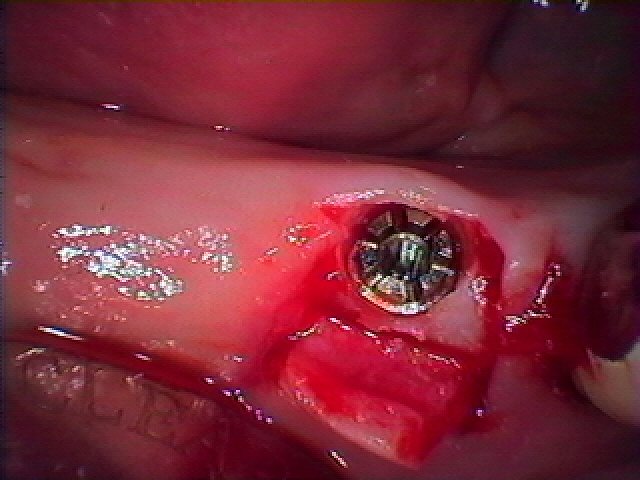

右下のインプラント埋入 インプラント埋入の実際|お知らせ |広島市安佐南区の歯科医院 右下のインプラント埋入 インプラント埋入の実際 トップ お知らせ・ブログ お知らせ 右下のインプラント埋入 インプラント埋入の実際 右下のインプラント埋入 インプラント埋入の実際 奥の歯がグラグラ ブリッジの支台歯 固いものが噛めない ブリッジを外しました ここに1本だけインプラント埋入を行っていきます 最小限で歯茎をめくります インプラントを埋入しています このように埋入しました 骨幅も狭くなり、神経に気を付けながら埋入しています 術前術後のパノラマになります 綺麗に埋入できています Web診療予約 初めての方へ 選ばれ続ける理由 院内設備について 歯が痛いしみる一般歯科 歯がぐらぐらする歯周病 健康な歯を保ちたい予防歯科 子供の虫歯予防をしたい小児歯科 銀歯をセラミックに審美歯科 白い歯を目指しませんか?ホワイトニング 矯正専門医がいるので安心矯正歯科 抜けた歯を補いたいインプラント・入れ歯 医院案内 スタッフ紹介 メリィハウス歯科クリニックオフィシャルホームページ ラベンダー歯科クリニックオフィシャルホームページ お知らせ・ブログ ホーム 診療科目 一般歯科 歯周病治療 予防治療 小児歯科 審美治療 ホワイトニング 矯正歯科 入れ歯・インプラント マウスピース矯正 初めての方へ 院長・スタッフ 設備紹介 医院案内・アクセス メニューを閉じる